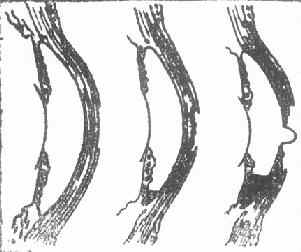

(二)进行期 如浸润阶段的炎症没有得到控制,浸润将蔓延扩大,随后新生血管将伸入浸润区,特别是周边部的炎症更是如此。在浸润区嗜中性白细胞溶解,释放出含有水解酶的溶酶体颗粒。水解酶与角膜蛋白发生反应,导致浸润区的角膜上皮层,前弹力层和基质层坏死脱落,角膜组织出现缺损,形成角膜溃疡(corneal ulcer),又称溃疡性角膜炎(ulcerativekeratitis),溃疡边缘呈灰暗色或灰黄色混浊。如溃疡向纵深发展,即形成深层溃疡,溃疡底部不平。由于毒素的刺激可并发虹膜睫状体炎;严重时,大量纤维蛋白性渗出物集聚于前房下部形成前房积脓(hypopyon)。当角膜基质完全被破坏、溃疡波及到后弹力层时,由于局部抵抗力降低,眼内压力可使后弹力层及内皮层向前膨出,称后弹力层膨出(descemetocele)。临床检查时在溃疡底部可见“黑色”透明小泡状突起。这是角膜即将穿孔的征兆。此时,若眼球受压,例如揉眼、碰撞、打喷嚏、用力咳嗽、便秘等,均可造成角膜骤然穿孔。在穿孔瞬间,病人可自觉眼部突然剧疼,并有热泪(即房水)流出。穿孔后可引起一系列的并发症和后遗症。

1、上皮脱落 2.溃疡及前房积脓 3.后弹力层膨出

图6-1 角膜溃疡

图6-2 角膜溃疡进行性演变